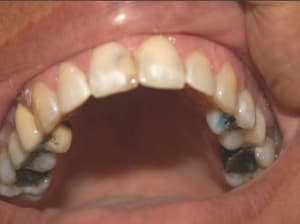

Cas_4_b_a1uady.jpg

Voir le message contenant cette image